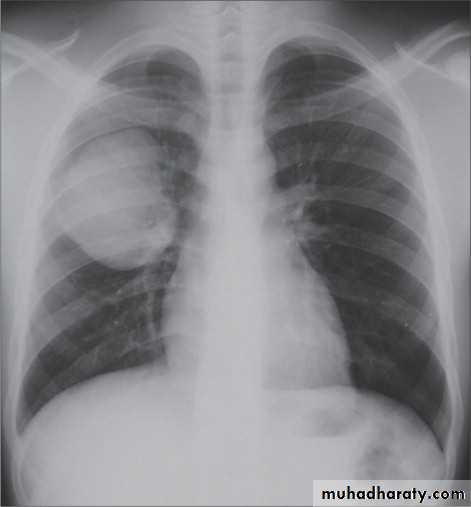

Mitral valve diseaseCXR of adult male , PA view shows: Enlargement of the cardiac shadow (cardiomegaly), Enlargement of left atrium Double density sign: the right side of the enlarged left atrium pushes into the adjacent lung and creates an addition contour superimposed over the right heart.

Mitral valve disease (double density RT cardiac border)CXR of adult , PA view shows: Cardiomegally Double density sign of right cardiac border Enlargement of left atrium, permenant left atrial appendage and relaced mitral valve (prosthesis)